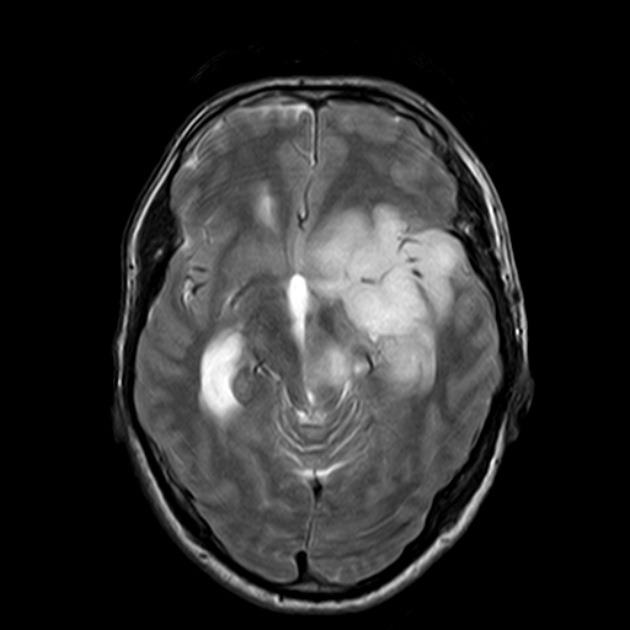

毛细胞星形细胞瘤约占全部儿童脑肿瘤的25%。在磁共振成像中,毛细胞星形细胞瘤通常是一种界限清楚的病变,通常具有囊性和结节状成分,可不均一地增...

毛细胞星形细胞瘤 是一种生长缓慢、边界较清的囊性星形肿瘤,是一种 良性胶质瘤 病理分型,WHO I级。 发病特点 毛细胞星形细胞瘤常发生于儿童和年轻人...

原发性脑肿瘤是儿童癌症相关死亡和发病的主要原因。毛细胞星形细胞瘤(Pilocytic astrocytomas, PAs)是国际卫生组织(WHO) I级肿瘤,是儿童主要的组织学亚型...

毛细胞星形细胞瘤(PA)以每年091/100,000的年龄调整发病率发生,是儿童和青少年中较常见的原发性中枢神经系统肿瘤。全部患者均接受了原发性切除或活检...